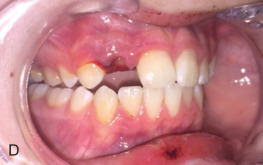

Next, each remaining tooth and restoration should be evaluated systematically (see Classification section ). Transillumination of visible light along the long axis of the tooth can identify subtle dental injuries to enamel. Each tooth should be evaluated for mobility, both individually or along with its adjacent teeth (indicating a dentoalveolar fracture). Mobility of an individual tooth can indicate luxation of the entire tooth or a root fracture that can require dental radiographs to diagnose. The clinician should then evaluate the alignment of the dental arches. Teeth are most commonly displaced in a buccolingual direction due to the vector of trauma perpendicular to the tooth’s long axis. A tilting of the occlusal plane can indicate luxation or intrusion injuries, but may indicate maxillary or mandibular fracture. Each tooth should be tested for mobility in all dimensions with care not to avulse loose teeth or dentoalveolar segments. A commonly used mobility index is the Miller classification, in which tooth mobility is evaluated using two hard objects (e.g. two tongue depressors). If a tooth is nondisplaced but mobile, this may indicate either preexisting periodontal disease or a crown/root fracture. Dental fractures more coronally positioned generally have more mobility.

Intraoral occlusal exam: The patient is instructed to carefully bring their teeth into occlusion with the clinician evaluating the movement. Premature occlusal contacts could indicate fracture or luxation injuries. The patient is then guided into their premorbid occlusion if tolerated. This allows the clinician to determine the complexity of restoring the patient’s dentition. Interferences of the palatal cusps of the molars with a seemingly intact mandible could indicate a palatal fracture with change in the transverse width of the maxilla.